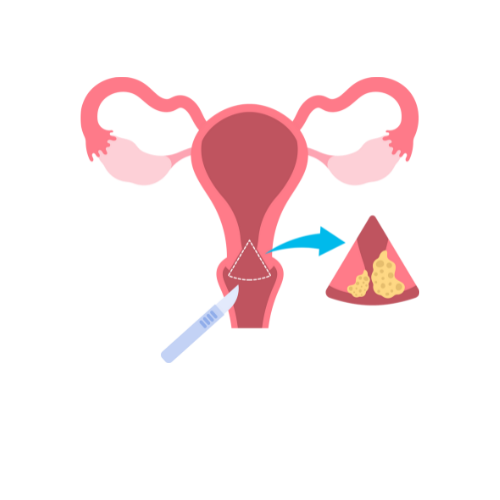

Endometrial Biospy

Our gynecologist offers endometrial biopsies, providing accurate diagnostic evaluations to assess the health of the endometrium and guide appropriate treatment plans for optimal reproductive health.